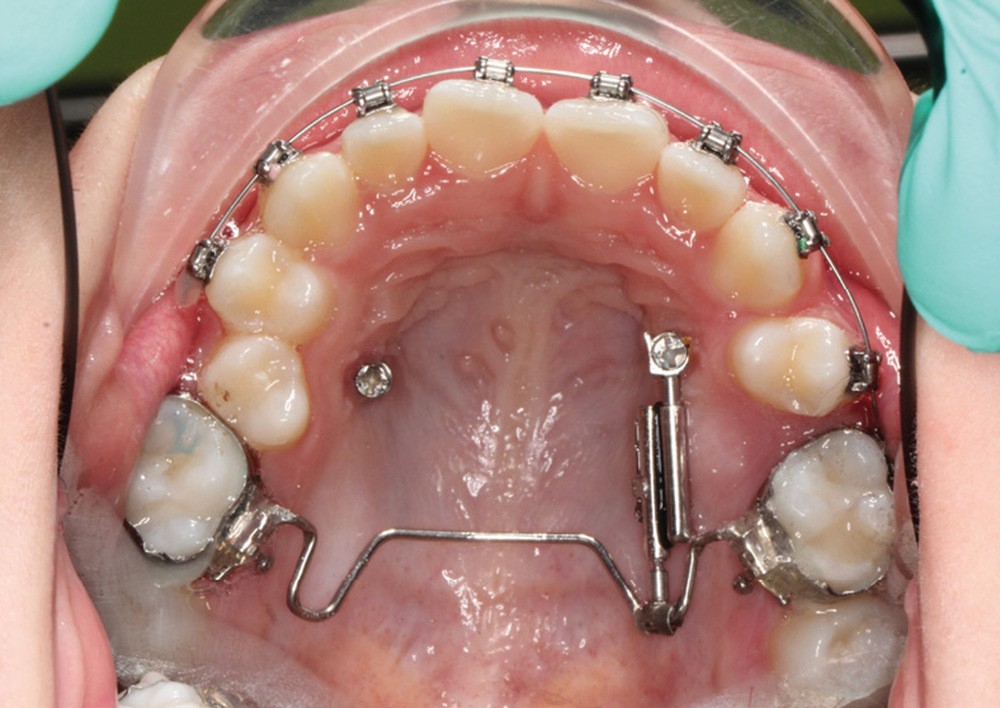

À côté de la coopération moindre qu’ils exigent, les ancrages squelettiques présentent également l’avantage de répondre à des indications très variées : correction des sourires gingivaux (Dr Skander Ellouze, fig. 3a-c), distalisation ou mésialisation molaire, supports pour les masques faciaux, mini transpalatin sur vis après expansion, ressorts de rétraction pour mettre en place les canines incluses sans léser les racines des dents adjacentes [3] (Dr Stéphane Renger, fig. 4) ou appareils d’expansion maxillaire (Dr Hans Winsauer, Dr Guido Sampersmans, fig. 5a-c)…